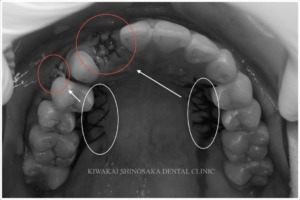

約2ヶ月後、手術箇所の生着を確認し、ジルコニアブリッジを作製、装着しました。

装着後は就寝時の歯軋りや食いしばりからブリッジを守るため、ナイトガードの使用をお願いしています。

患者さまにはその後、6ヶ月に1回の定期的なメンテナンスを受けていただいており、良好な状態を維持しています。